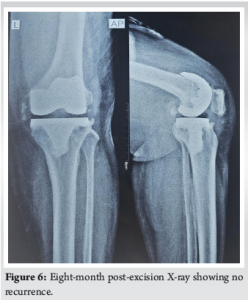

The patient underwent conservative management with regular physiotherapy to maintain joint mobility and analgesics for pain relief. Surgical excision of the ossified tissue was not performed to allow HO to mature. Gradual improvement in knee function over the following months was observed. At 1-year follow-up, full knee extension was obtained; however, restricted flexion was present with no significant improvement observed (Fig. 3 and 4). The patient was advised to undergo excision at the end of 1 year. Following excision, radiotherapy with a single cycle of 75cGy was given in the immediate post-operative period. Chemoprophylaxis with indomethacin 75 mg given once daily for 3 months and discontinued. The wound healed well, and the patient showed symptomatic improvement with a 20° increase in ROM during the initial post-operative period (Fig. 5). At 8 months post-excision, there is no radiographic evidence of recurrence (Fig. 6), and the range of knee flexion has further improved to 80°. The patient remains symptomatically more comfortable following the excision.

HO is the development of bone in tissues where it normally does not develop and, often, after surgical trauma, inflammation, or local tissue injury [5]. In TKR, surgical manipulation, disruption of the periosteum, and soft-tissue trauma can all set up an environment for ectopic bone formation, primarily through osteoinductive factors such as bone morphogenetic proteins and inflammatory cytokines. HO occurrence after TKR is less common, with the reported prevalence from 1% to 3%. The patient had limited knee flexion and pain on occasion from the HO impinging against the quadriceps mechanism, an extremely rare and unusual complication. Most patients have asymptomatic or very mild stiffness post-TKR, so this presentation was unique. Without identifiable predisposing factors, such as prior HO, trauma, or systemic conditions, the patient had severe functional limitations that demonstrate the unpredictable behavior of HO. Early detection is key in the management of HO, and this was exemplified by the progressive imaging findings in this case. There was a hazy appearance at 5 weeks post-onset that progressed to well-formed ossification at 3 months. These findings underscore the value of routine post-operative follow-up to detect complications early and intervene appropriately. Conservative management strategies range from physiotherapy, analgesics, and/or medications such as indomethacin or bisphosphonate to maintain mobility of the joint as well as limit further ossification [7]. Prophylactic radiotherapy offers a potential option to inhibit further ossification, but its application post-diagnosis remains debated. Current evidence supports its use within a narrow window-either preoperatively or immediately postoperatively-rather than after ossification has formed [8]. Immediate surgical excision of HO diagnosed early is generally not recommended, as immature ossification carries a higher risk of recurrence and bleeding. Waiting for the ossification to mature, typically over 6–12 months, allows for better demarcation of the mass and reduces the risk of surgical complications. Surgical excision is best reserved for cases of mature HO that cause significant pain or functional limitations, as it provides better outcomes and minimizes recurrence risks [9]. In this case, operative treatment was effective after a period of 1 year, so that the patient could obtain satisfactory recovery with full extension and increased flexion compared to pre-operative status (Fig. 5 and 7).